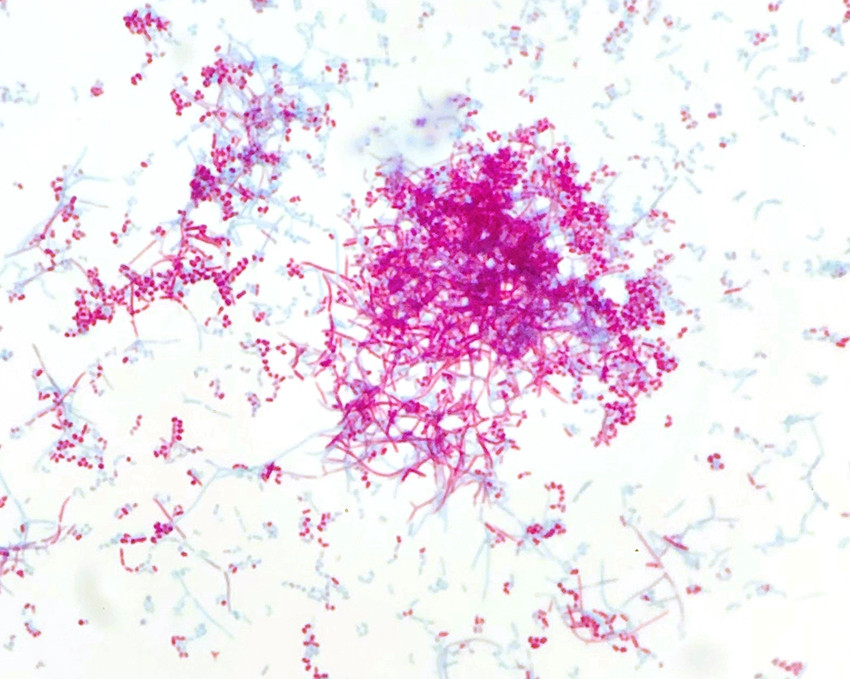

Nocardia spp. are strictly aerobic, gram-positive, rod-shaped bacteria. Species in the genus are often slow-growing, and prolonged incubation times (7–10 days) may be required. The microbe grew on blood agar and was visible as dry chalky-white colonies after just 2 days (Figure 3). Microscopic examination of the colonies revealed gram-positive branching filamentous rods, which were partially acid-fast on Ziehl-Neelsen staining (Figure 4). Nocardia spp. are environmental bacteria found in soil and water worldwide. There are more than 80 different Nocardia species, of which at least 30 cause disease in humans, the most common being the N. asteroides complex, N. brasiliensis and N. farcinica (11).